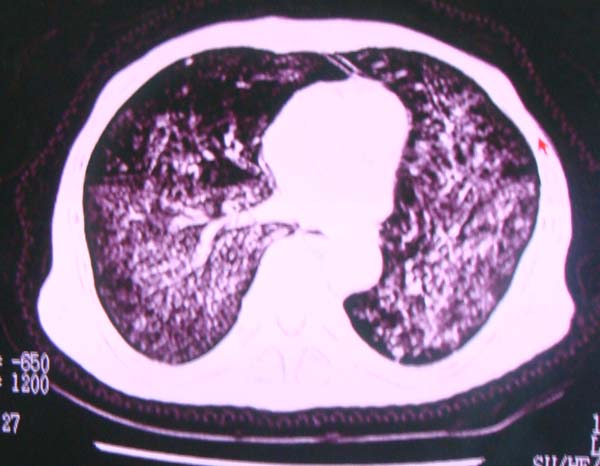

以下是引用zhangzhongshou在2008-2-15 22:25:00的发言:[br]片子照得不清,基本考虑1、细支气管肺泡癌2、亚急性血行播散型肺结核。请结合临床。片子细节显示不清,无法提供进一步意见。

以下是引用杀毒软件在2008-2-15 22:34:00的发言:[br]小叶中心性肺气肿。两肺弥漫性病变,肺泡微石病,过敏性肺炎,尘肺2期,特发性肺纤维化都有可能。[br]不象肺泡癌。